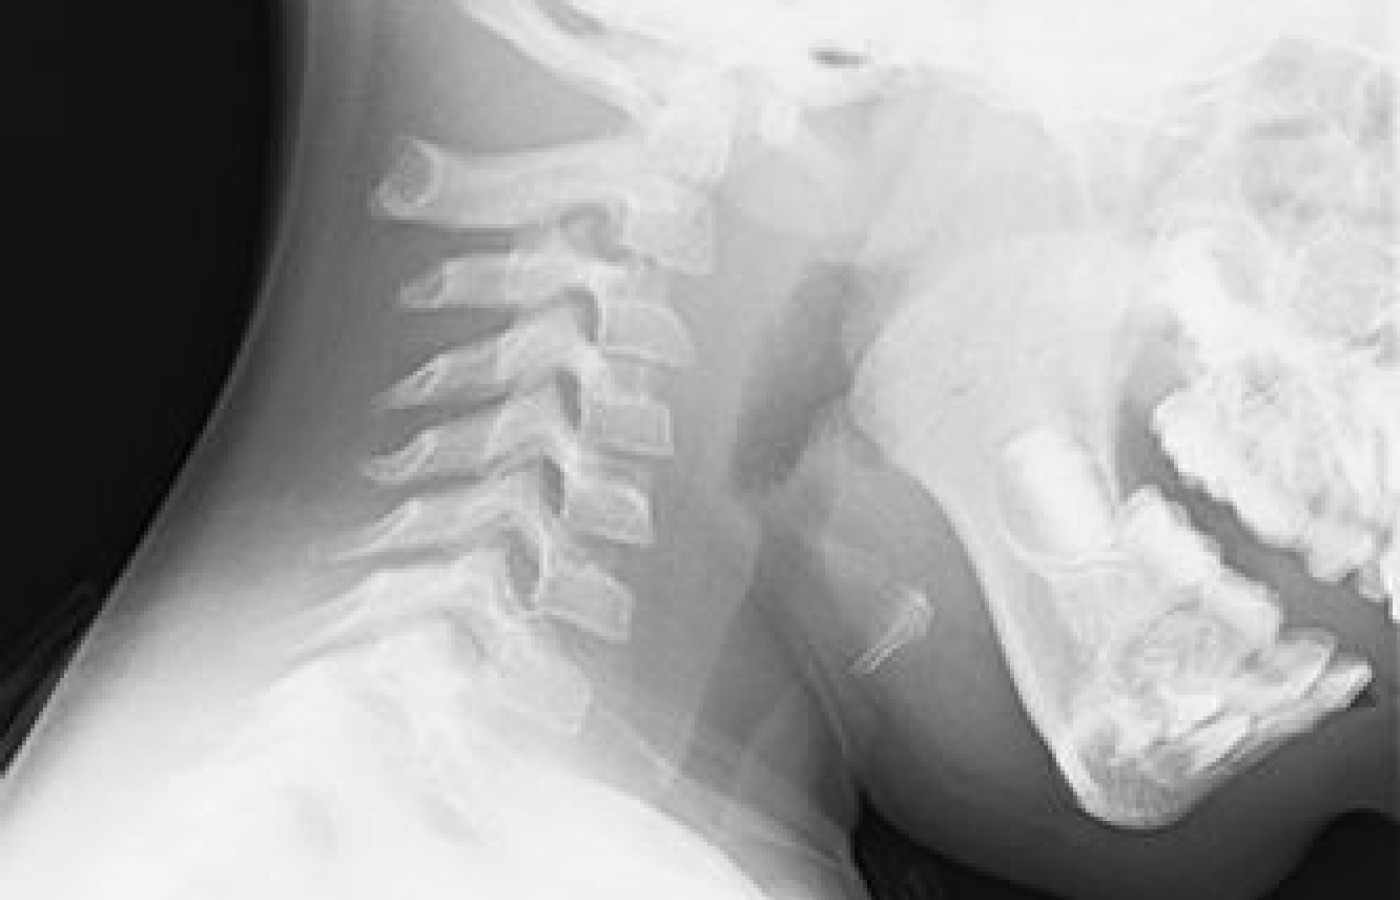

Review the cervical flexion radiograph in Figure 1A. The patient has an increased atlantodental interval (ADI) at C1-C2. Now review the cervical extension radiograph of the same patient in Figure 1B. The ADI decreased. Why?

The answer: The joint between the atlas and the odontoid process of the axis is unstable. In this case, the instability is in a patient with Down's syndrome. Ten to 20 percent of Down's patients are missing the transverse ligament that stabilizes the atlantodental articulation.

During the initial patient examination, if imaging is performed, usually the traditional AP, APOM and lateral view series, instability may or may not be identified. An increased ADI can be observed on a neutral lateral view, but not always.

For this reason, the traditional three-view series plus flexion and extension views are recommended for patients with Down's, rheumatoid arthritis, or significant head and neck trauma.